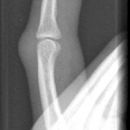

Mittelgliedbasisfraktur

Es wurden keine Bilder gefunden.